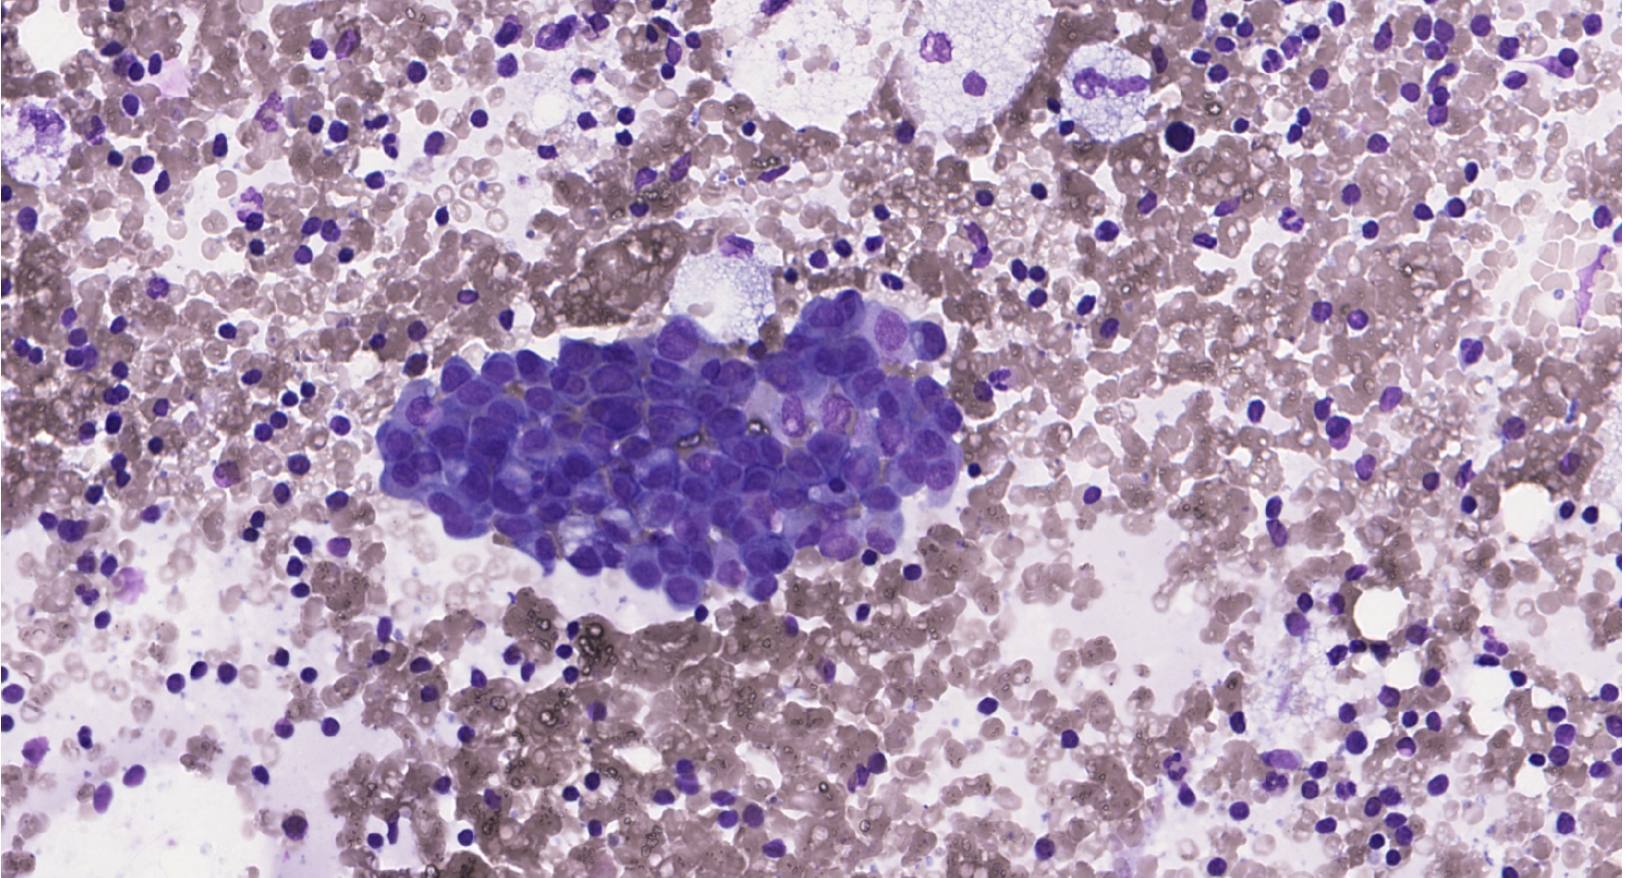

This is a 77-year-old woman with a 10-mm BI-RADS 4 mass in the upper inner quadrant of

the left breast. Core needle biopsy shows invasive carcinoma of no special type (NST),

Nottingham grade II (Elston–Ellis). Hormone receptors positive (100%), HER2 1+, Ki-67

20%. Homolateral axillary lymph node ultrasound demonstrates cortical thickening to 4

mm. An ultrasound-guided fine-needle aspiration of the atypical lymph node was performed.

Two direct smears were prepared and stained with MGG.